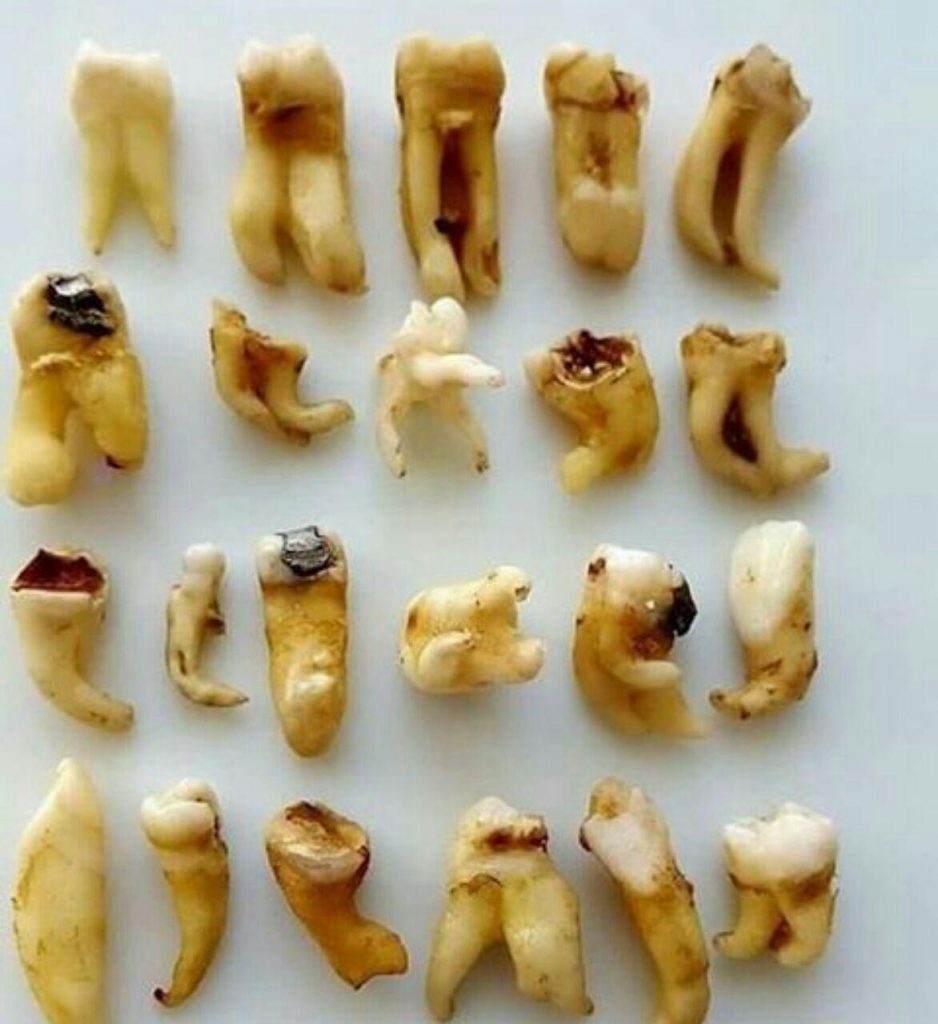

ترمیم و زیباییدندانپزشکی اطفال _ عصب کشی

پروتزهای دندانی (ثابت و متحرک )

جراحی لثه _ لمینیت _ کامپوزیت ونیر